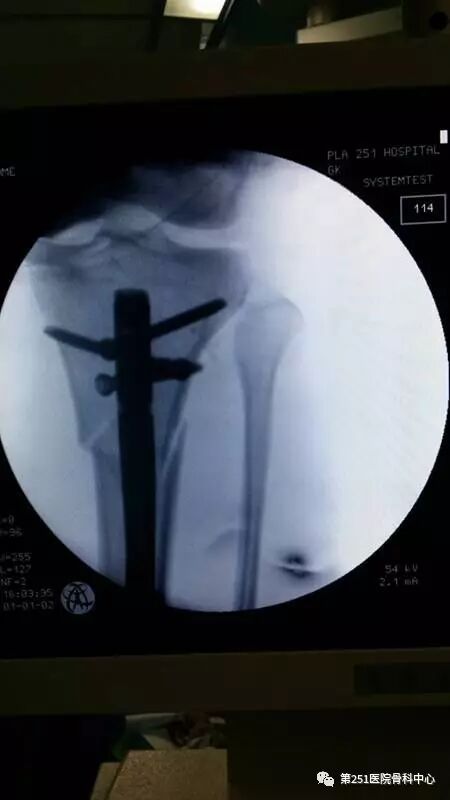

病例1:男性,40岁,车祸伤,胫腓骨多段骨折。

![]()